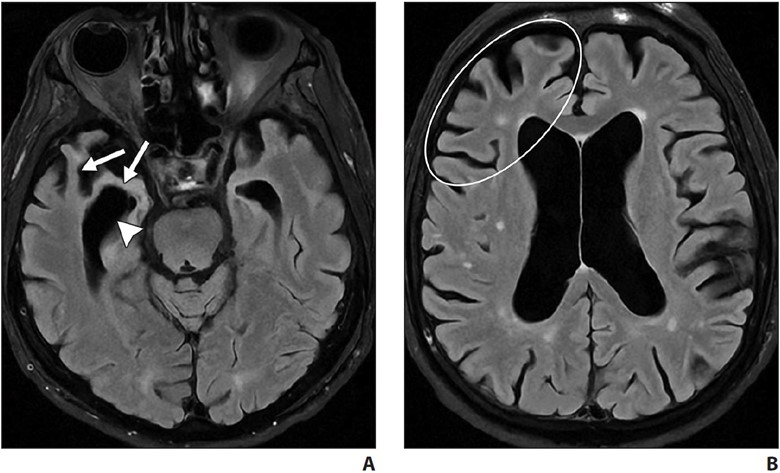

Behavioral variant frontotemporal degeneration is the most common form of FTLD and is characterized by the gradual onset and progression of changes in personality, behavior, and executive function with relative sparing of memory and visuospatial functions (in contrast with AD). The frontal and temporal lobes are characteristically involved [7, 19, 20]. MRI shows atrophy with knife-edge gyri. On ASL and FDG PET, there is hypoperfusion and hypometabolism of the frontal and temporal lobes (Fig. 5) with relative sparing of the parietal lobes (in contrast with AD).

A and B, Axial FLAIR MR images of patient with personality changes show markedly asymmetric right temporal lobe and mildly asymmetric right frontal lobe atrophy. Note thinning of right temporal lobe gyri (arrows, A) and asymmetric dilatation of right temporal horn (arrowhead, A). Note asymmetric prominence of right frontal lobe sulci (oval, B) compared with left frontal lobe sulci.

Semantic variant PPA primarily presents with anomia and single-word comprehension deficits. Volume loss affects the ventral and lateral portions of the anterior temporal lobes (Fig. 6).

A and B, Axial FLAIR (A) and sagittal T1-weighted (B) MR images in patient with anomia and single-word comprehension deficits show asymmetric and profound anterior temporal lobe atrophy (oval, A). Note marked anterior temporal lobe gyral thinning (arrowheads, B).

In most patients, the left hemisphere is predominantly affected, although bilateral involvement may be seen. Asymmetric hippocampal volume loss is commonly seen on the side where temporal lobe atrophy is present. Tar DNA-binding protein of 43 kilodaltons (TDP-43) proteinopathy is the most common underlying neuropathology [22, 23].